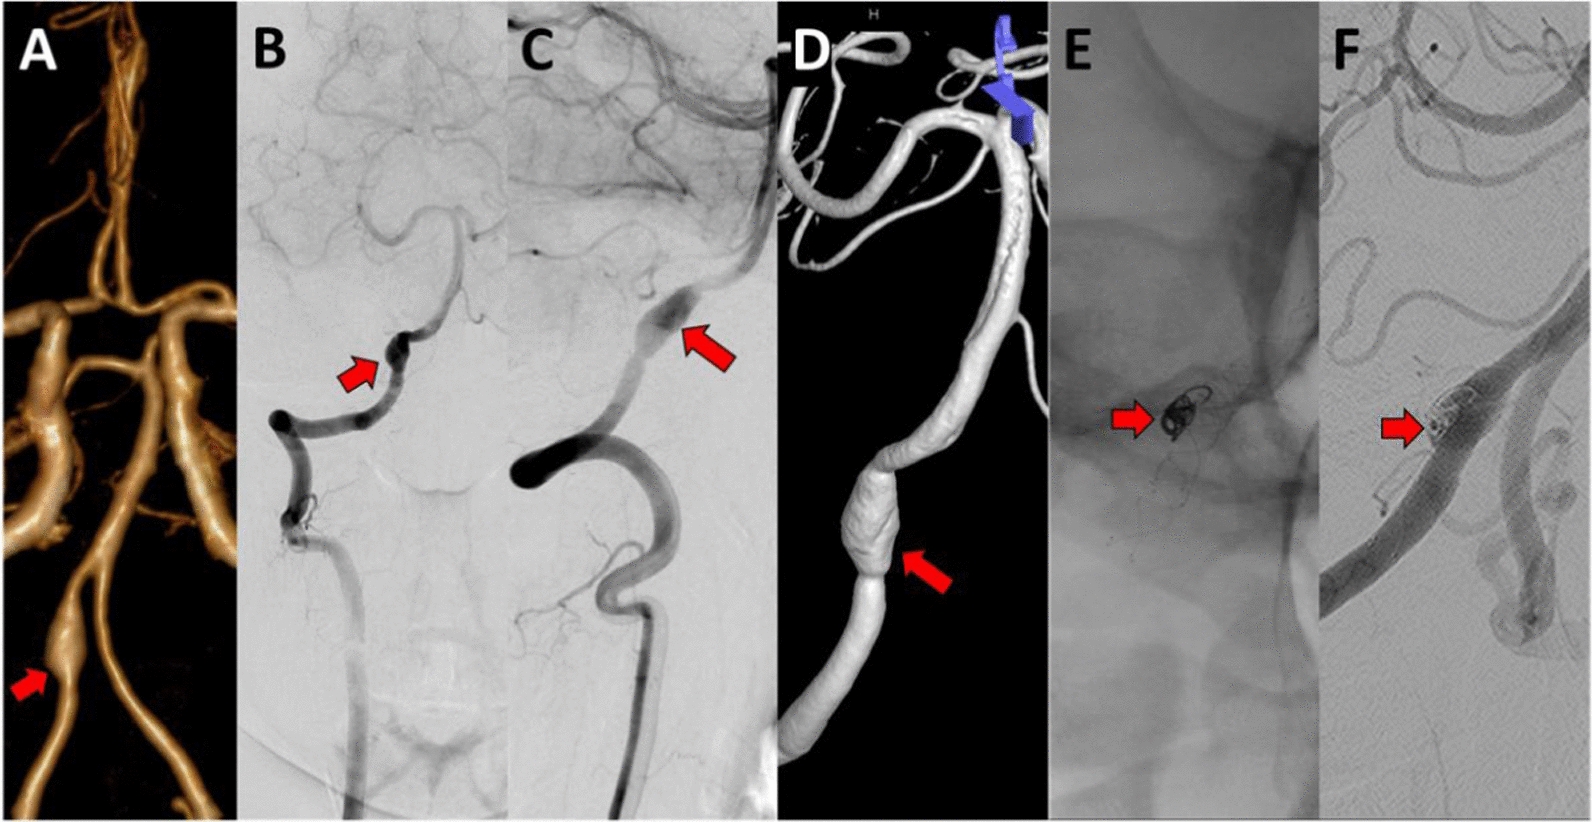

Direct anticoagulant (DOAC) administration is advised in stroke or transient ischemic attack cases instead of vitamin K antagonists. A study conducted by Engelter et al., on 194 patients with CAD failed to show non-inferiority of aspirin to anticoagulants where the primary endpoint in the form of a composite clinical outcome (stroke, bleeding, and death) occurred in 21 (23%) patients in the aspirin group compared to 12 (15%) of 82 patients in the anticoagulation group in patients with cervical artery dissection (CAD) (absolute difference 8% [95% CI –4 to 21] [20]. However, in cases of extracranial dissection, dual antiplatelet administration with aspirin and clopidogrel is recommended for several weeks. As a comparison, according to the AHA/ASA guideline for secondary prevention of acute stroke, patients with acute stroke or TIA within 3 months after the acute event can be given antiplatelets (aspirin) or anticoagulants (warfarin) [21]. Figure 3 shows the management therapy for VAD with fusiform dilatation aneurysm with double antiplatelet therapy (DAPT).

Fig. 3

A Case of Vertebral Artery Dissection with fusiform dilatation aneurysm treated with DAPT. A 69-year-old man, with severe headaches and a history of hypertension ( +). As seen by C-DSA neuroimaging: A. A fusiform dilatation aneurysm of VAD at the Rt-VA, segment V4 from AP View of C-DSA; B. A fusiform dilatation aneurysm of VAD at the Rt-VA, segment V4 from AP View of C-DSA Roadmap; C. A fusiform dilatation aneurysm of VAD at the Rt-VA, segment V4 from Lateral View of C-DSA; D. A fusiform dilatation aneurysm of VAD at the Rt-VA, segment V4 from Lateral View of C-DSA Roadmap. (The red arrow shows the dissecting fusiform dilatation aneurysm of the right vertebral artery.)